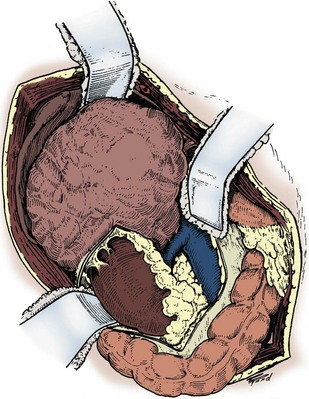

Figure 54–90 After the pedicle is secured and the ureter divided, the kidney is mobilized outside the Gerota fascia.

(Reproduced with permission from Novick AC, Streem SB, Pontes E, editors. Stewart’s operative urology. 2nd ed. Baltimore: Williams & Wilkins; 1989.)

Figure 54–91 Remaining medial vascular attachments are secured and divided to complete the nephrectomy.

After dividing the renal pedicle, the kidney is mobilized outside the Gerota fascia with blunt and sharp dissection. Any remaining vascular attachments are ligated with nonabsorbable sutures and divided. The ureter is ligated and divided. The kidney and adrenal gland are removed. A Penrose drain is placed in the empty renal fossa and externalized through a separate stab incision. The abdomen is closed in layers as previously described.